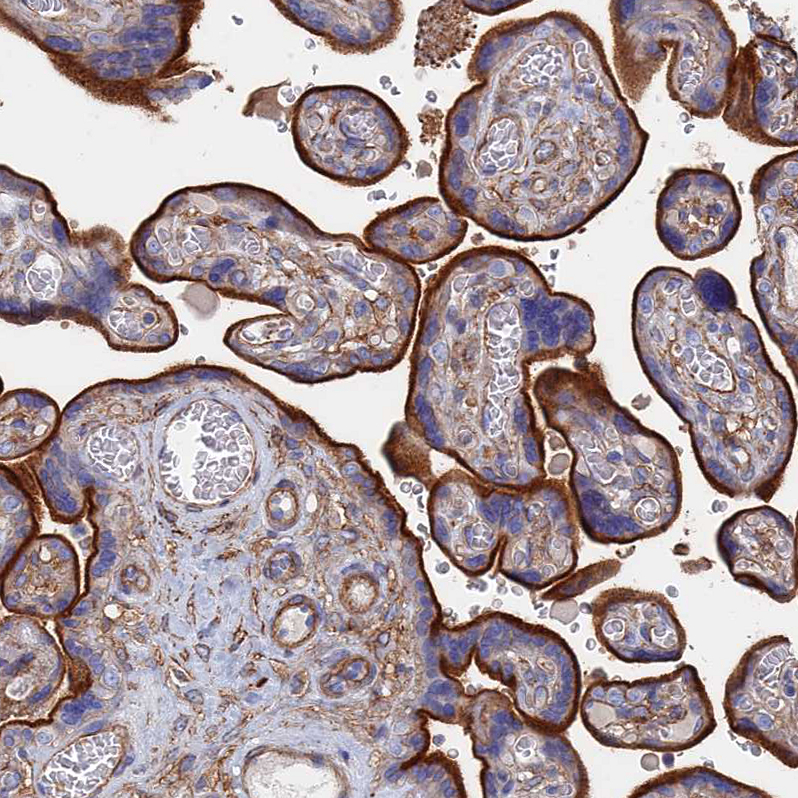

Immunohistochemical staining of human placenta shows strong membranous positivity in trophoblastic cells.